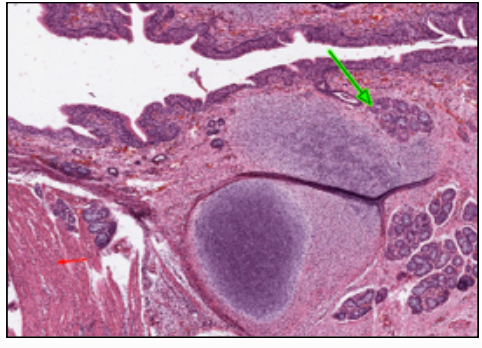

MALT NODULE (@ TRACHEA)

LYMPH NODE = discrete, encapsulated collection of lymphoid tissue

MALT NODULE = no capsule, intimately related to epithelium